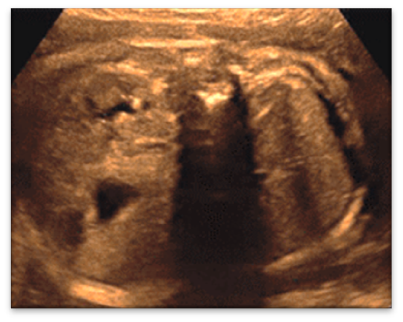

IPKD (ARPKD)

ADPKD